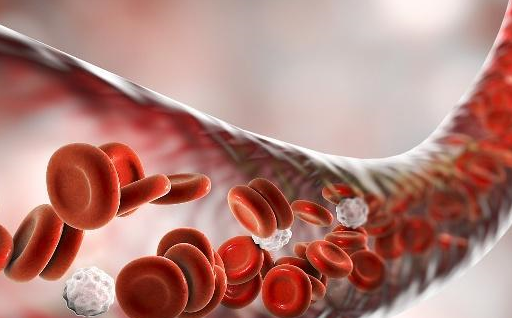

立即阅读补气血别只知道阿胶!常吃这3样养气血,手脚暖气色佳越吃越年轻